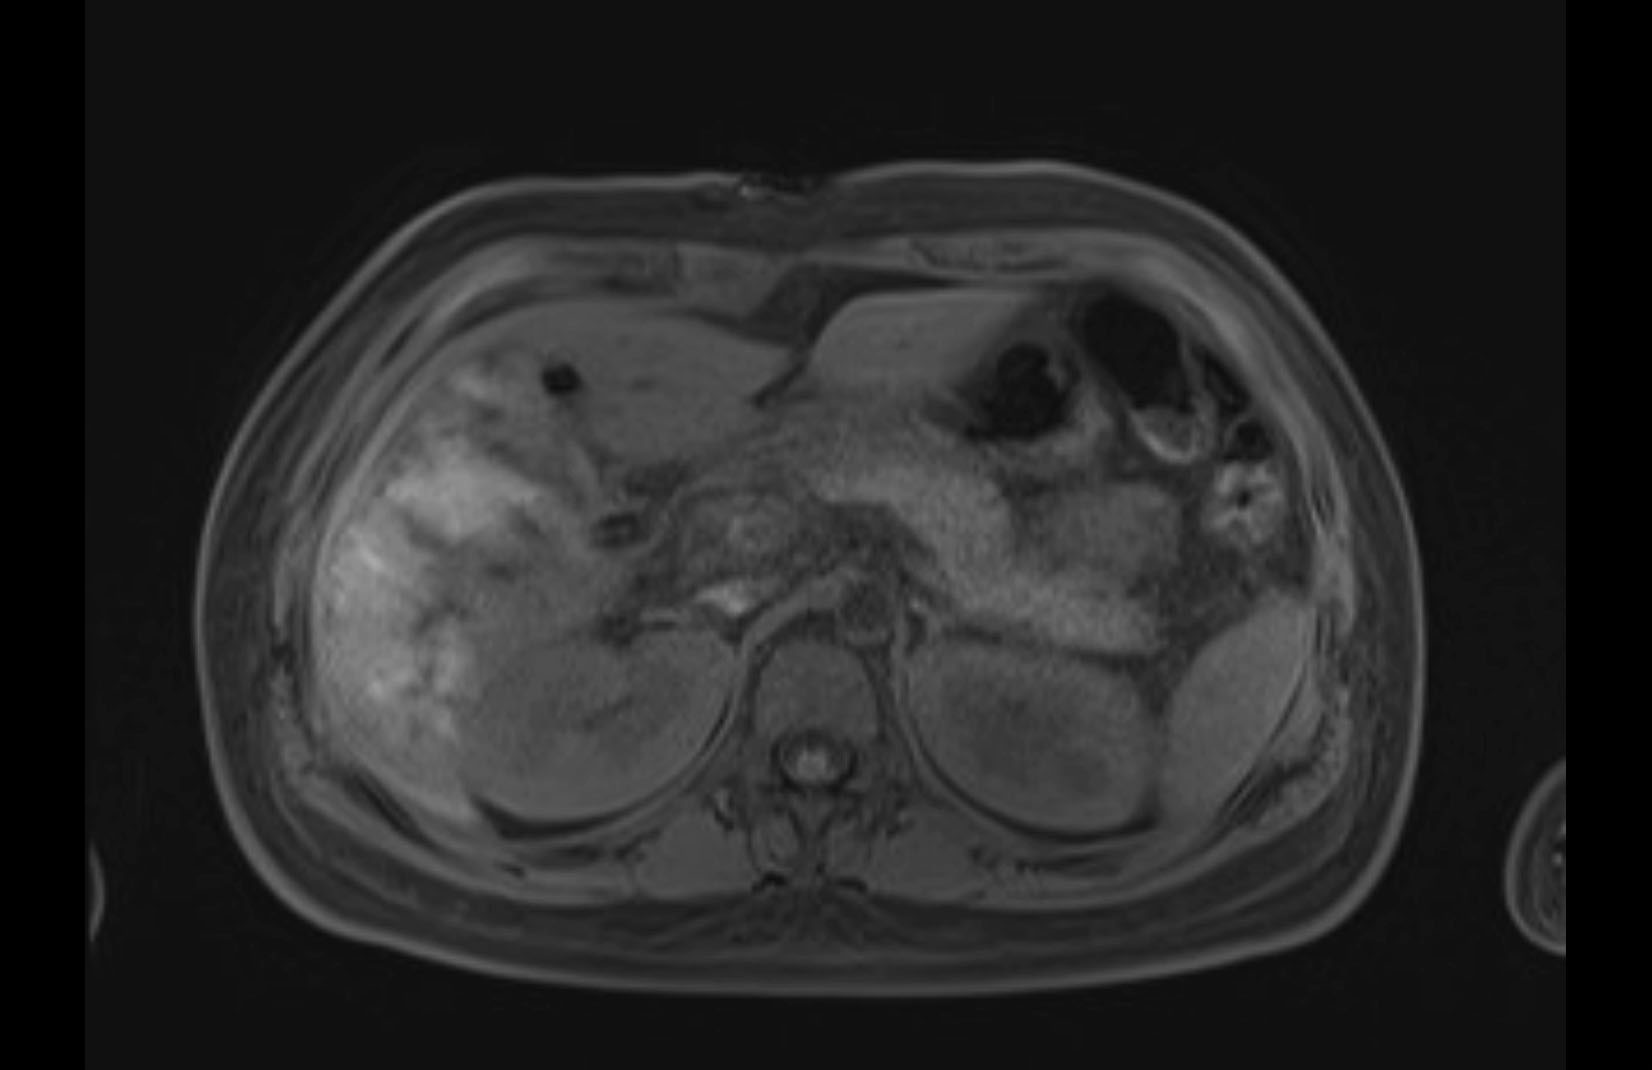

Imaging Analysis

Look through the patient's CT scan to identify any areas of concern for the necessary procedure.

MRI T1

Based on initial findings, which issue(s) would you be most concerned about?